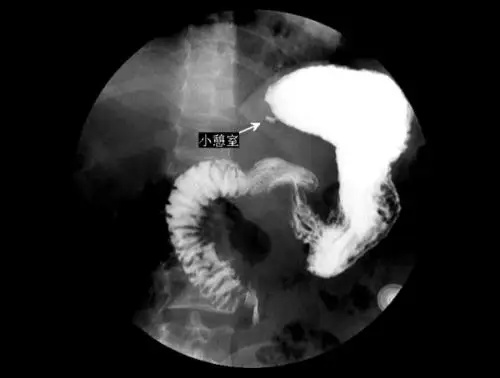

消化道轮廓的改变 龛影(niche)是指钡剂涂布的轮廓有局限性外突的

憩室是个啥玩意儿?